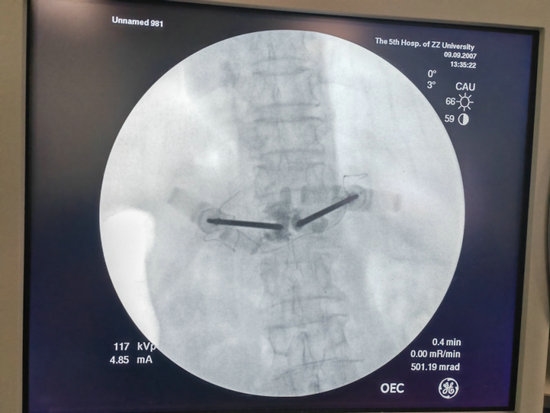

经皮穿刺椎体骨水泥成形术是一项在局麻下即可完成的手术,仅需要在背部伤椎相对应的位置切2个1cm左右的小口,然后将穿刺针穿刺到椎体前1/3的深度。

在透视确认位置良好后,即可注入骨水泥,待确认骨水泥完全凝固后,去除穿刺针,包扎伤口,手术就结束了。